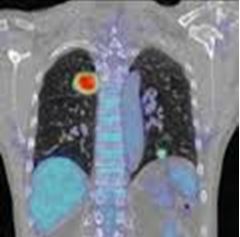

Ghi hình phát hiện các khối u trong phổi, YHHN đã và đang phát triển mạnh. Hiện nay SPECT, SPECT/CT, PET và PET/CT đã cho những hình ảnh định lượng về giải phẫu và chức năng cụ thể, nâng cao hiệu quả chẩn đoán và điều trị. Dưới đây ví dụ vài hình ảnh cụ thể:

PET/CT ghi hình u phổi

Đặc biệt hiện nay, PET/CT trên thế giới và ở Việt Nam đang phát triển và ứng dụng nhiều và có hiệu quả cao trong chẩn đoán, theo dõi đáp ứng điều trị và tiên lượng trong các bệnh về phổi .